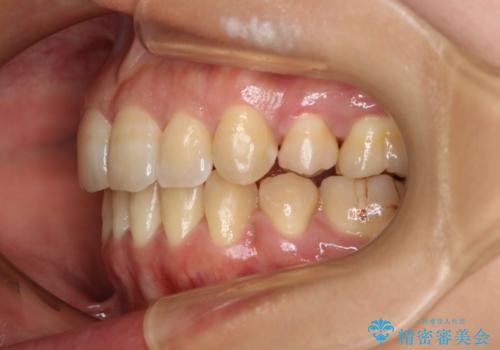

前歯を後ろに下げたい ワイヤー矯正(クリア装置)

- 前歯を後ろへ下げることを主訴に来院された患者様です。

10代の時に非抜歯でワイヤー矯正をしていました。

口元の突出感の改善や歯の移動量などを考慮し、抜歯を伴うワイヤー矯正での治療を選択しました。

抜歯を行うことで前歯を後ろへ下げるスペースを獲得し、口元の突出感や歯のガタつきを改善していきました。